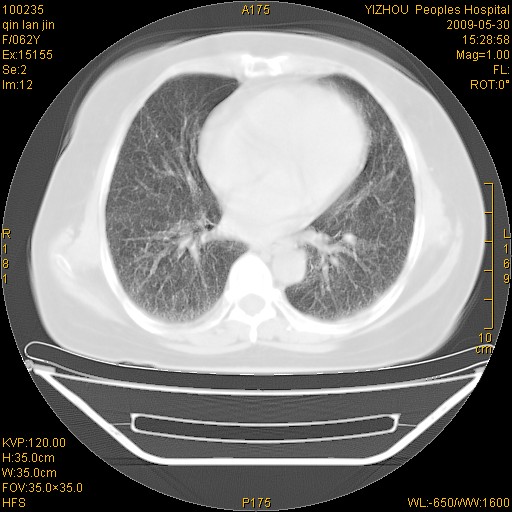

弥漫性双肺间质纤维化。

两肺弥漫性间质性病变(间质性肺炎伴肺间质纤维化?)。

弥漫性双肺间质纤维化

支持弥漫性肺间质纤维化。

间质性肺炎伴肺间质纤维化。